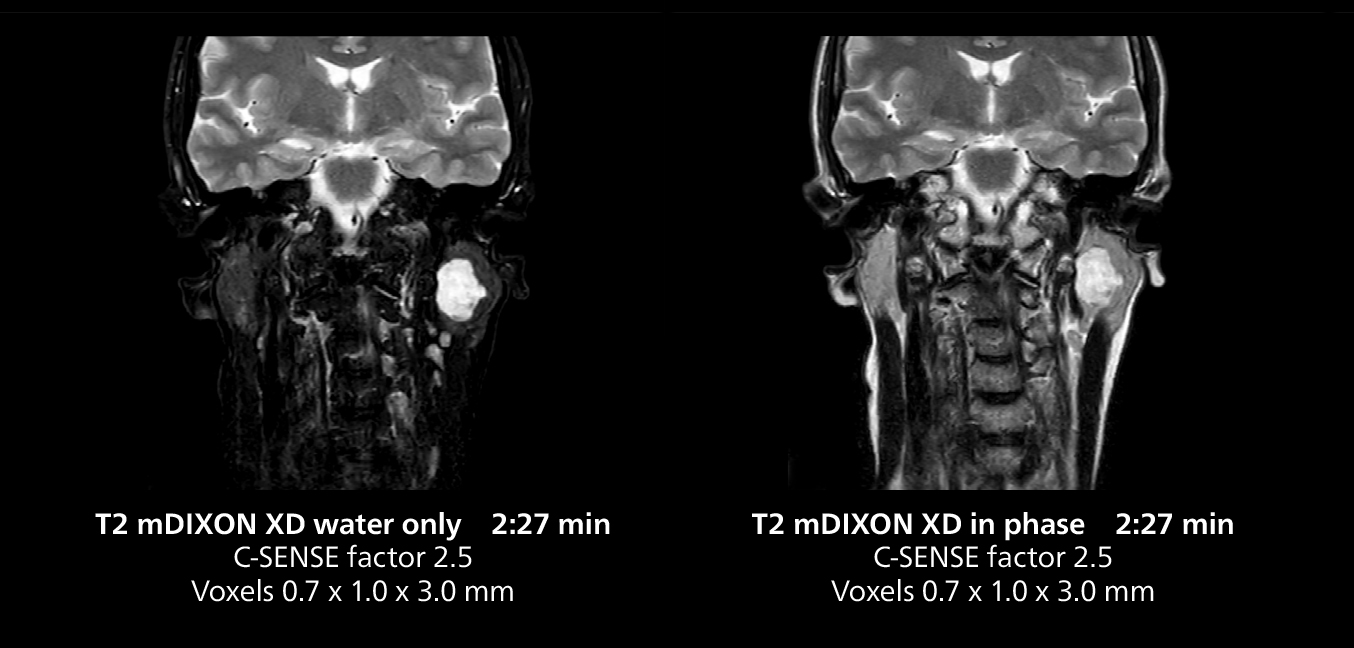

Salivary gland imaging on MR 5300

This MRI case illustrates imaging of salivary gland abnormalities with different sequences. Compressed SENSE allows to accelerate scanning while maintaining high quality. With mDIXON XD, different contrast types can be obtained from scanning one sequence.

Salivary gland imaging on MR 5300

This MRI case illustrates imaging of salivary gland abnormalities with different sequences. Compressed SENSE allows to accelerate scanning while maintaining high quality. With mDIXON XD, different contrast types can be obtained from scanning one sequence.